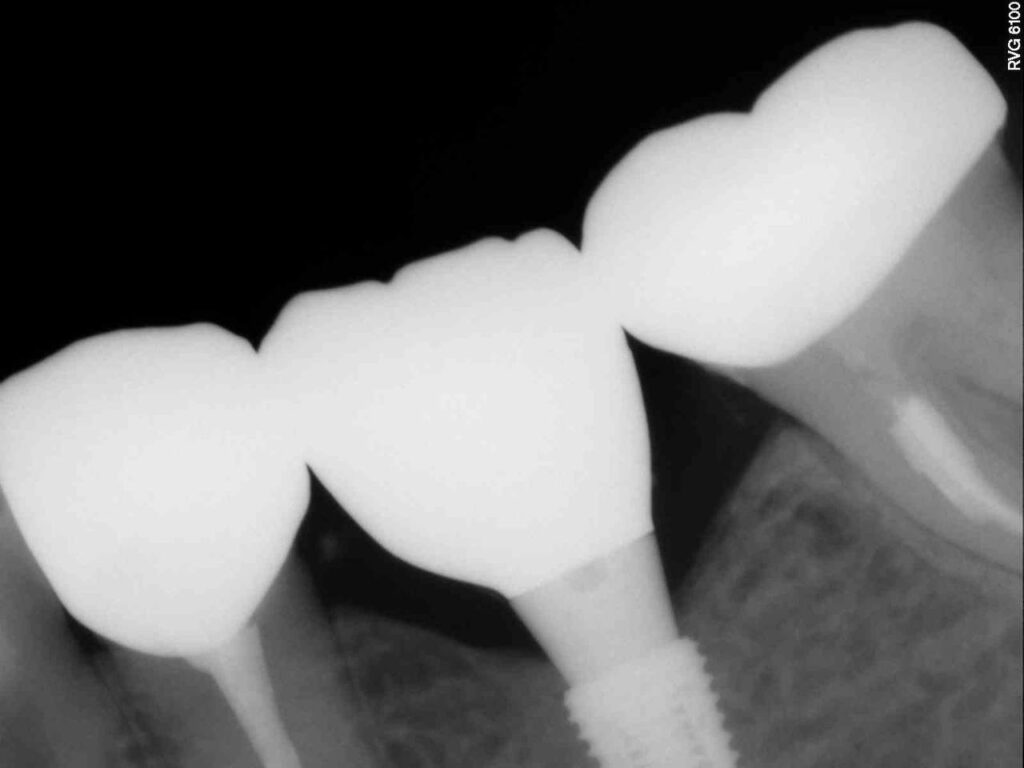

Протезирование коронками из диоксида циркония, после эндодонтического лечения — Исламов Л.А.(01.04.2026)